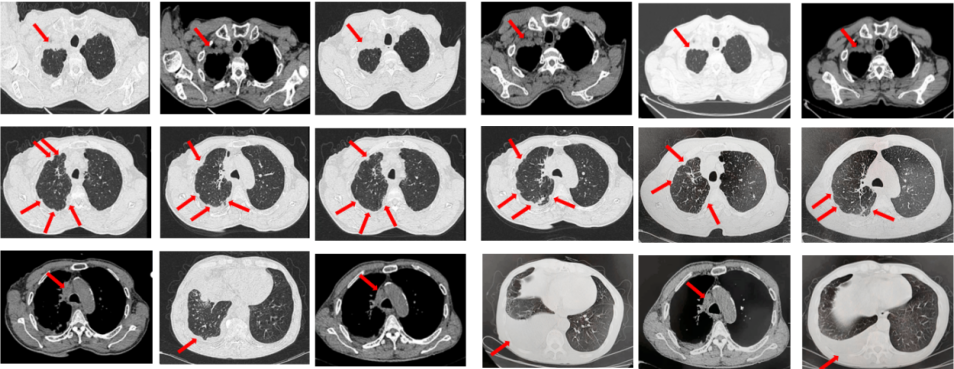

2023年9月复查评效PD。成功入组“一项开放、多中心对比谷美替尼与多西他赛在既往接受免疫治疗和含铂双药化疗后进展的驱动基因阴性且伴有MET扩增的局部晚期或转移性非小细胞肺癌患者中的随机对照III期临床研究”。成功随机到试验组,口服谷美替尼至2024年10月,期间复查最佳评效PR。

图3:A.二线治疗后病情进展,右肺上叶新发肿物较前明显增大,新发无症状脑转移病灶;B.经谷美替尼(300mg po qd)治疗3个月后复查肺内病灶及颅内病灶较前明显缓解

2024年10月复查出现PD,后因患者病情迅速恶化进入肿瘤姑息治疗。该患者的全部诊治经过如图4所示。